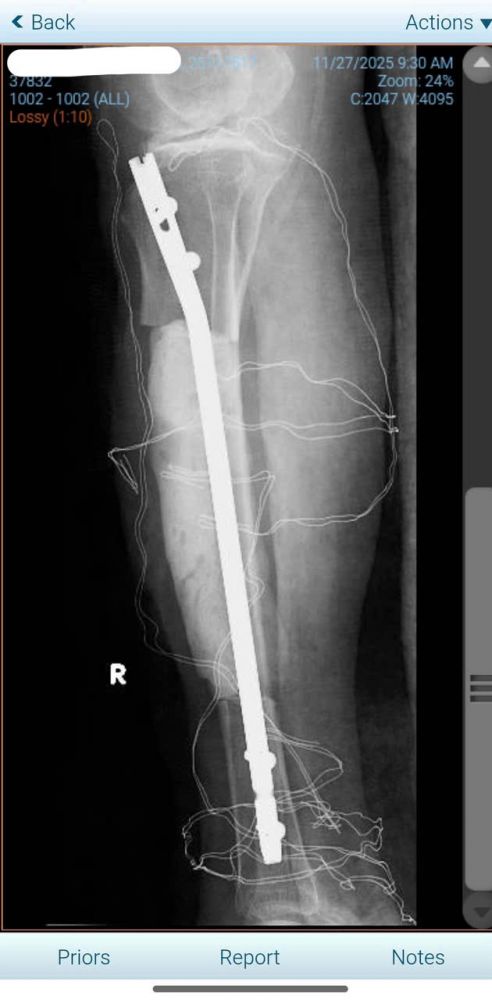

Hình 5: Phần xương chày còn lại được giữ trục bằng đinh nội tủy

--Xử lý xương: Đóng đinh nội tủy để cố định trục chi, kết hợp đắp Cement spacer (xi-măng kháng sinh) vào phần khuyết xương để giữ trục và ngăn ngừa nhiễm trùng.